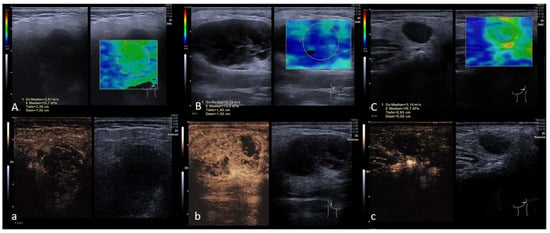

2.3. Shear Wave Elastography

2.4. Perfusion Analysis